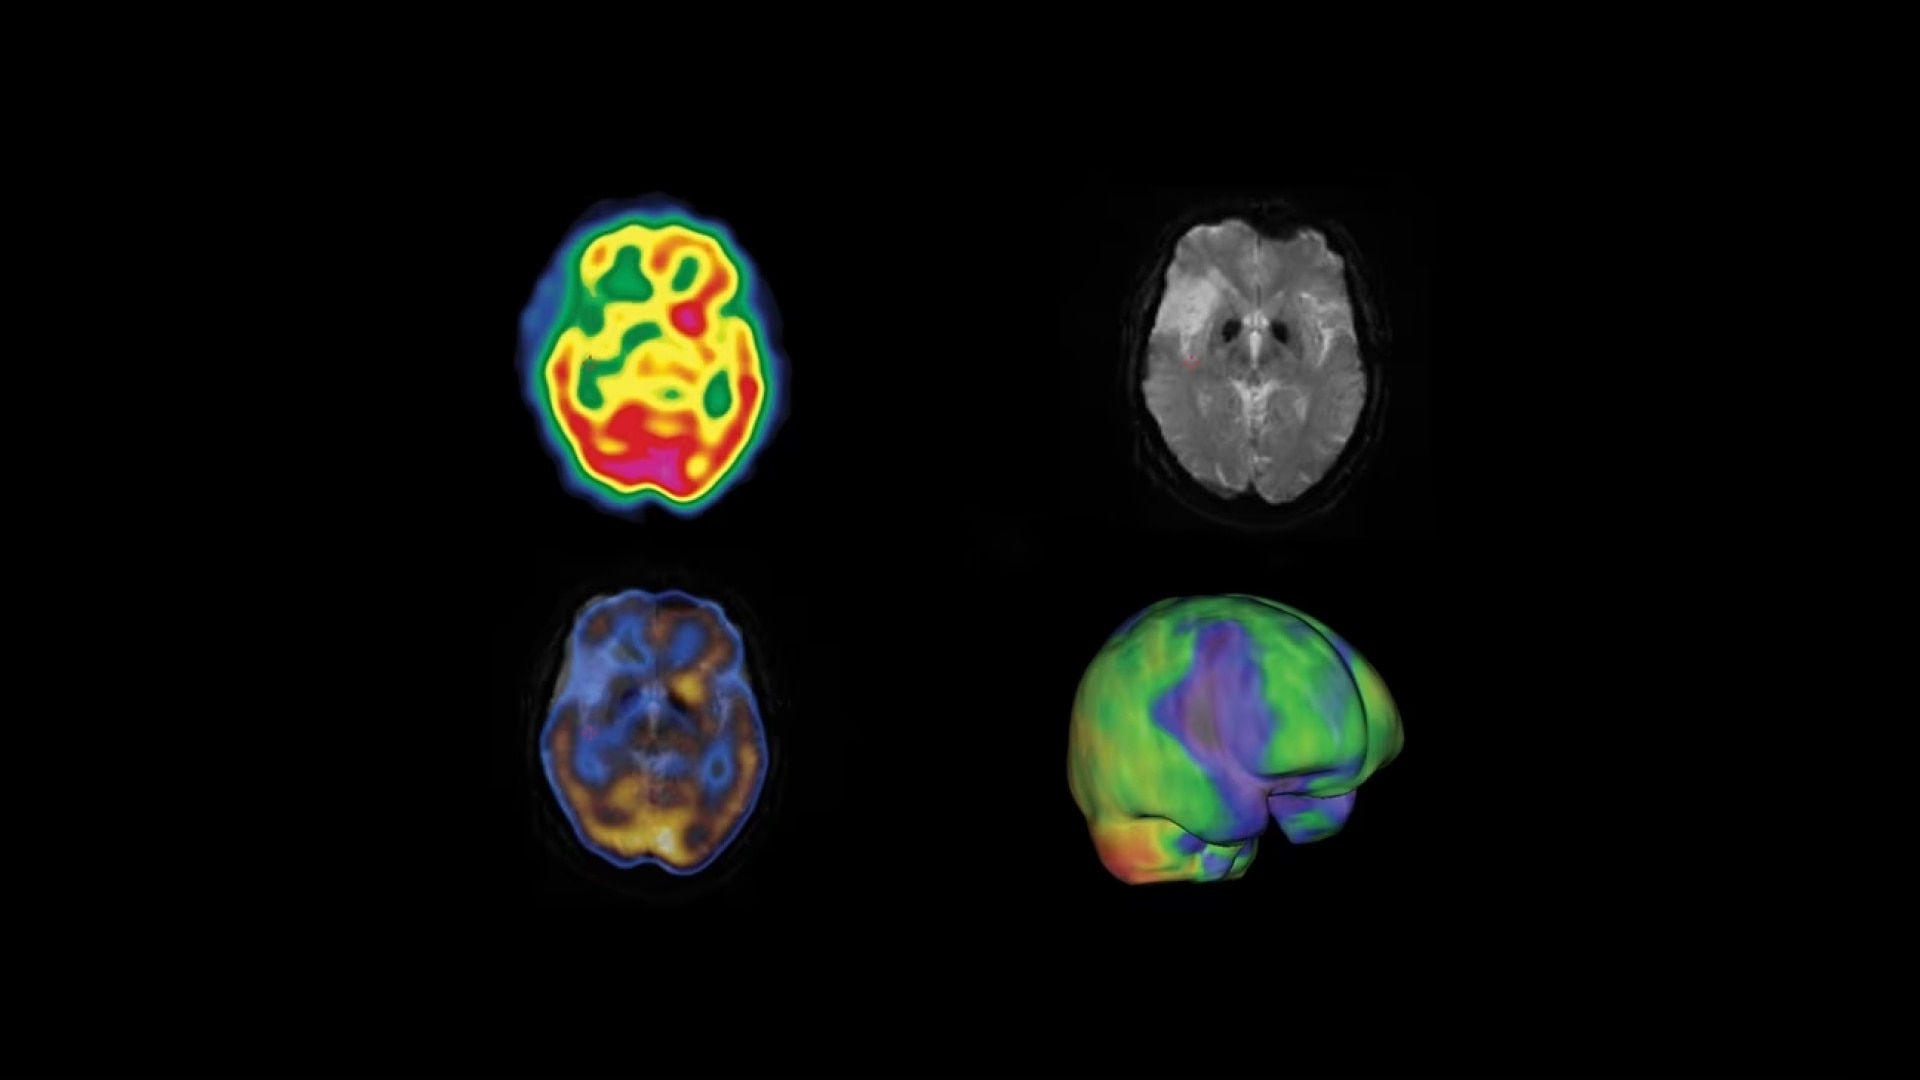

A fully digital vision for nuclear medicine

A fully digital vision for nuclear medicine